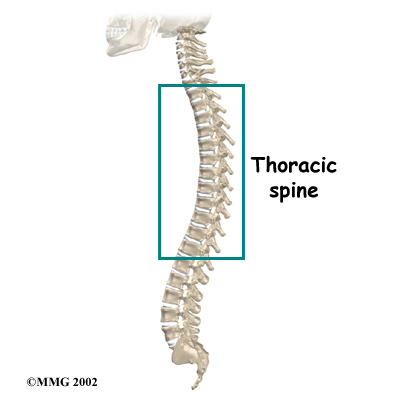

The human spine is made of 24 spinal bones, called vertebrae. Vertebrae are stacked on top of one another to create the spinal column. The spinal column gives the body its form. It is the body's main upright support.

The main section of each vertebra is a large, round structure called a vertebral body.

Compression fractures cause this section of bone to collapse. When the fracture is due to osteoporosis, it usually occurs in the lower part of the thoracic spine, near the bottom of the rib cage.

A bony ring attaches to the back of each vertebral body. When the vertebrae are stacked on one another, the bony rings form a hollow tube. This tube, or canal, surrounds the spinal cord. The spinal cord is like a long wire made of millions of nerve fibers. Just as the skull protects the brain, the bones of the spinal column protect the spinal cord.

Your physical therapist will prescribe exercises for you to do in the clinic and also to be done as part of a home program. Exercises that improve the range of motion in your back, neck, shoulders as well as your hips may be prescribed. If your compression fracture was from osteoporosis, then the extension motion of your upper back (thoracic spine) will be of paramount importance. As mentioned above, wedge compression fractures of the thoracic spine from osteoporosis often lead to a flexed back posture. The risk of losing the ability to function in the upright extended position is high so maintaining this motion is crucial. Even the proper use of your shoulder joints will suffer if the spine loses extension therefore exercises may also be prescribed to maintain shoulder function. Neck range of motion can also be affected if the flexed posturing becomes severe thus range of motion exercises for the neck may also be required. Hip range of motion deficits will be addressed as normal hip range of motion allows the spine to move more freely and decreases the stress on the spinal joints. Patients with traumatic stress fractures don’t often present with the wedge shaped fractures and therefore the primary focus will be the recovery of all ranges of motion, not just thoracic extension.

Your physical therapist will prescribe exercises for you to do in the clinic and also to be done as part of a home program. Exercises that improve the range of motion in your back, neck, shoulders as well as your hips may be prescribed. If your compression fracture was from osteoporosis, then the extension motion of your upper back (thoracic spine) will be of paramount importance. As mentioned above, wedge compression fractures of the thoracic spine from osteoporosis often lead to a flexed back posture. The risk of losing the ability to function in the upright extended position is high so maintaining this motion is crucial. Even the proper use of your shoulder joints will suffer if the spine loses extension therefore exercises may also be prescribed to maintain shoulder function. Neck range of motion can also be affected if the flexed posturing becomes severe thus range of motion exercises for the neck may also be required. Hip range of motion deficits will be addressed as normal hip range of motion allows the spine to move more freely and decreases the stress on the spinal joints. Patients with traumatic stress fractures don’t often present with the wedge shaped fractures and therefore the primary focus will be the recovery of all ranges of motion, not just thoracic extension.